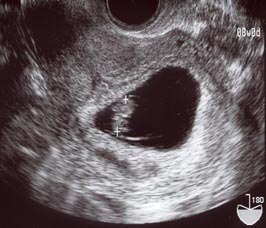

またですよ…(8w6dくらい)

2006/07/06 (Thu) - 妊娠初期(~15w)

今日は出勤するつもりだったのになぁ…(おいおい)。

お化粧途中でもよおしてトイレへ…

したらば!

また茶色のオリモノさんご降臨!!

おなかもちょっと痛いような気がするのでお休みしました。

しかし、どうして病院が休みの木曜に出血したりするんだろう…。

酷くならないように祈るしかないっすね…。